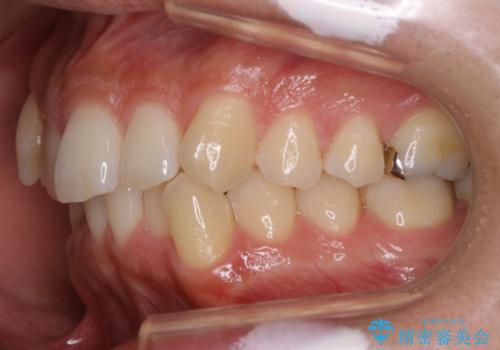

インビザラインで八重歯の治療

八重歯と噛み合わせえお治す必要がありましたが、抜歯を必要とするほどの状態ではなかったため非抜歯プランで治療を開始しました。

マウスピースとマイクロインプラントを組み合わせることで、抜歯をしなくても歯並びを治すためのスペースを作ることができます。奥歯から順に移動させていくので前歯に変化が出るまでには時間がかかりますが、その分健康な歯を抜歯することなく理想的な歯並びを手に入れることができます。